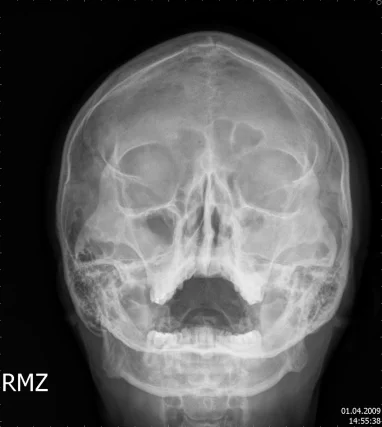

【110-2 醫學(六) 第72題】16歲男孩,主訴鼻塞、濃稠鼻涕已經超過一年。根據此張X光片,最可能的診斷是: